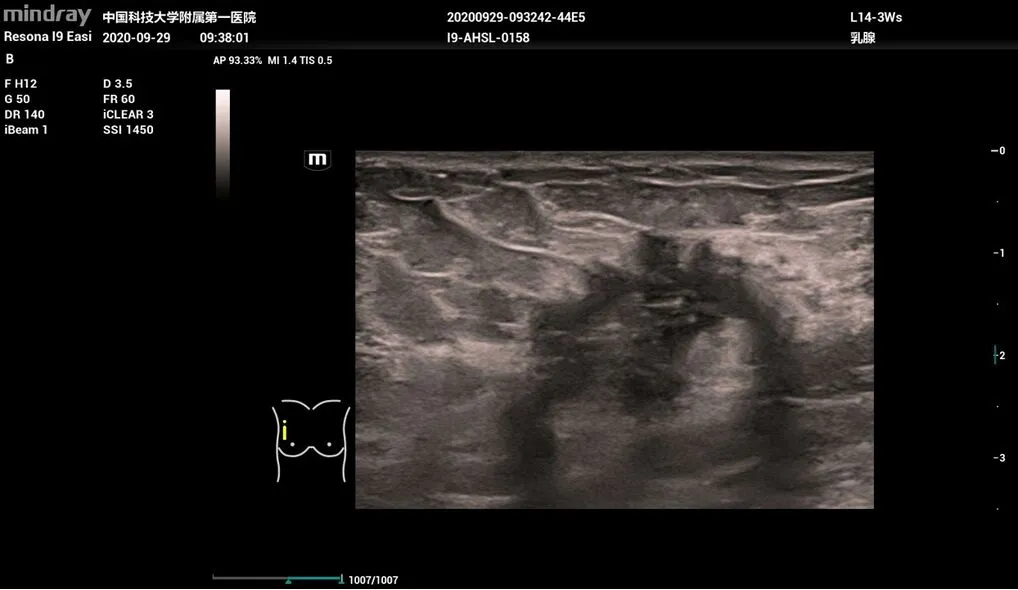

Диагностика заболеваний молочной железы Smart Breast

Resona I9 позволяет проводить интеллектуальный анализ молочной железы по шкале BI-RADS, включая полностью автоматическое обнаружение, измерение, аннотирование, анализ поражений, составление отчётов. Протокол ориентирован на очаги поражения, что повышает контроль качества. Множественные поражения могут исследоваться в нескольких плоскостях для получения более полных данных.

- L14-3Ws – линейный датчик для исследования сосудов, органов брюшной и грудной полости, педиатрии.

Рак груди, 2D, L14-3Ws